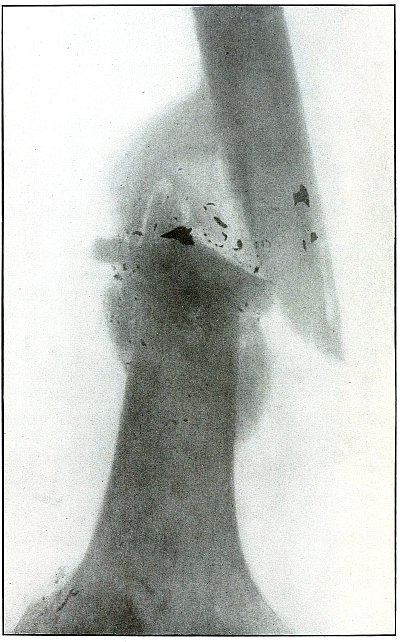

As the bullet is undeformed and its penetrating power very slight, its

velocity was that of extreme range.

The emergency treatment, is, of course, a simple antiseptic dressing

with the leg held in the most comfortable position by muscular action.

The subsequent treatment is removal of the bullet when proper surgical

conditions obtain.

[Pg 130]

Plate 60.

[Pg 131]

Rifle—Plate 60.

LOWER EXTREMITY.